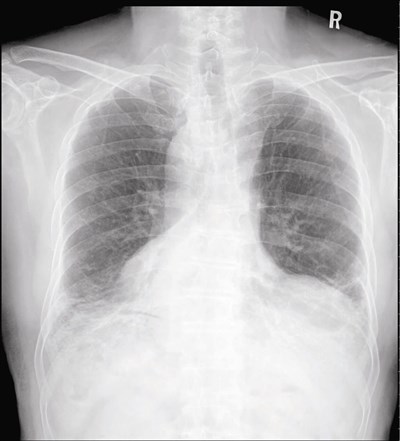

乾燥症看起來不嚴重,但若不積極治療,將影響其他器官,造成肺纖維化。圖/台北慈濟醫院提供

乾燥症看起來不嚴重,但若不積極治療,將逐漸影響其他器官,造成肺纖維化、血管炎、腎小管酸血症及神經病變等,少部份患者會合併甲狀腺瘤、淋巴瘤或其他器官的腫瘤,必需要多加小心。